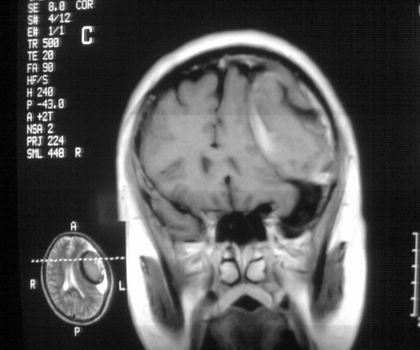

以下是引用影像孺子牛在2008-4-29 21:20:00的发言:[br]首先病变定位在脑外,根据ct密度及mri信号特征考虑慢性硬膜下血肿不连续环形钙化。

以下是引用周战梅在2008-4-29 23:12:00的发言:[br]脑外病变,蛛网膜下腔增宽,囊壁点状、环形钙化,增强扫描呈不均匀环状强化,考虑为囊性脑膜瘤可能性大,慢性脓肿、血肿机化、胆脂瘤不能除外。